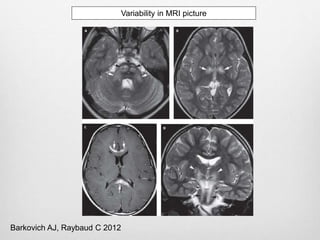

Variability in MRI picture

Barkovich AJ, Raybaud C 2012